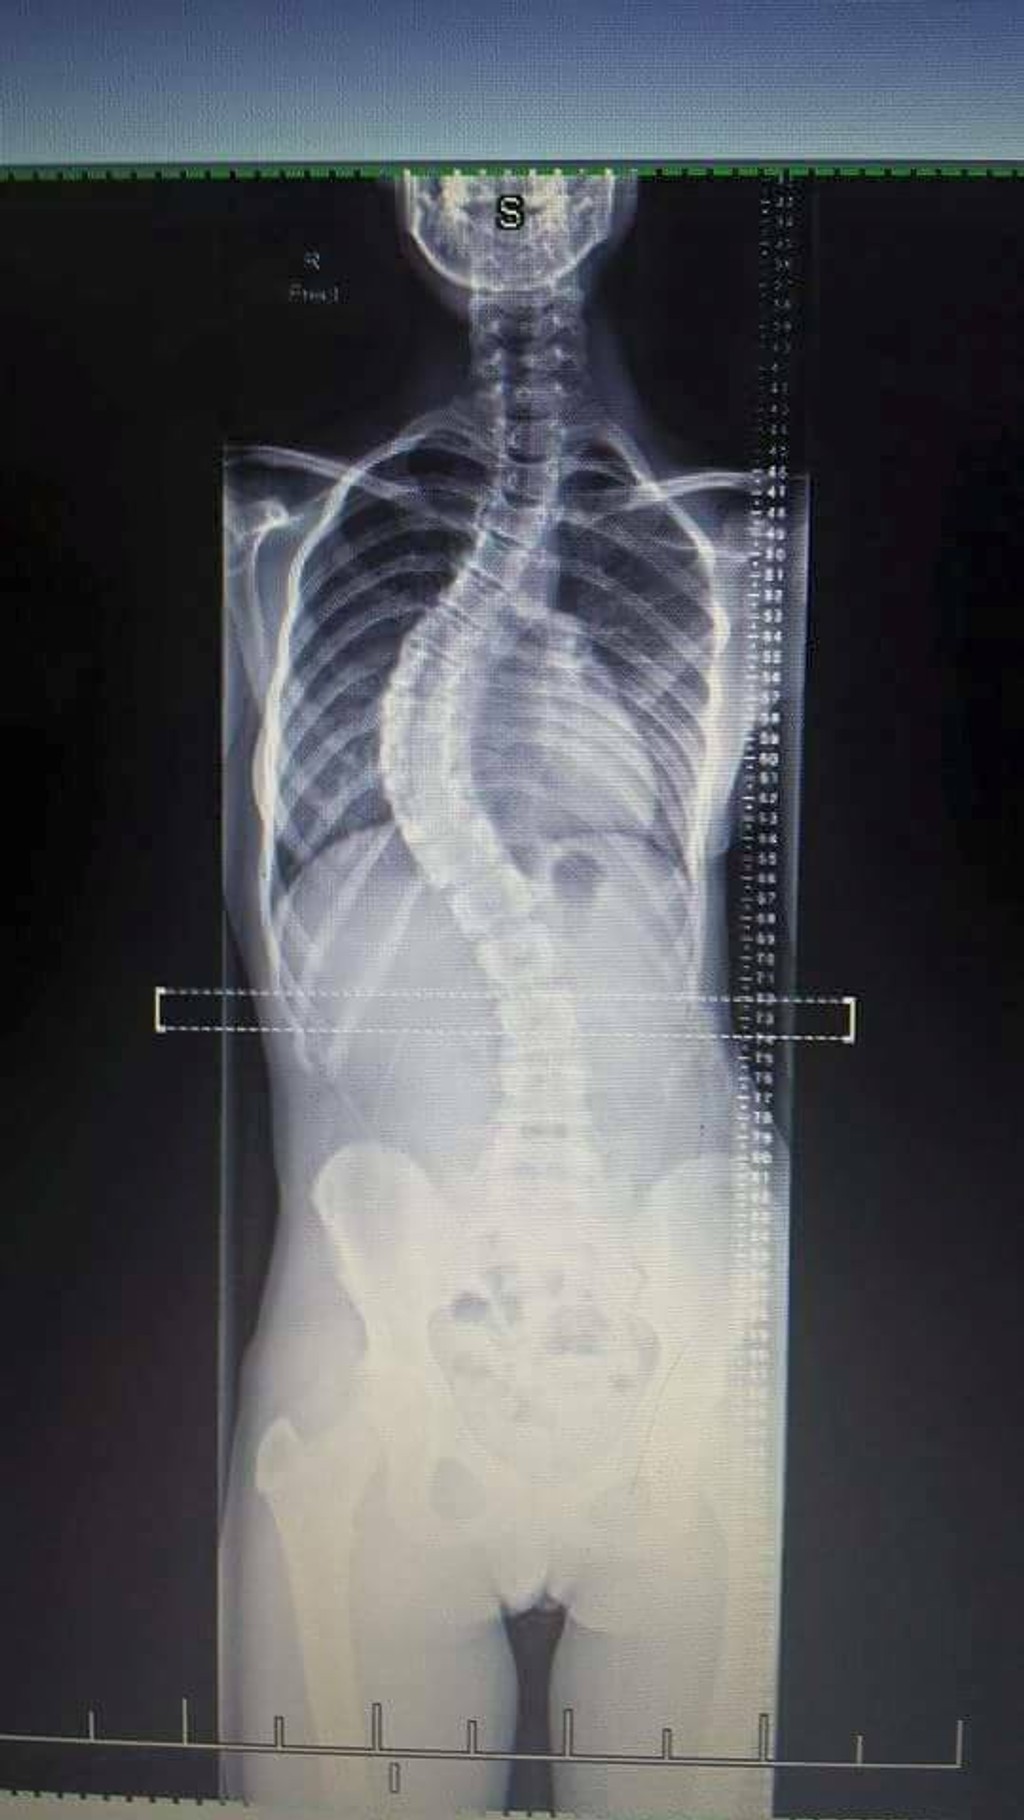

Sam Hansen a jej chrbtica predtým a teraz.

Mladá Novozélanďanka Sam Hansen má vzácnu chorobu. Ide o idiopatickú skoliózu. Chrbticu mala vykrivenú o 55 stupňov. Prvýkrát si to všimla, keď mala dvanásť rokov a chcela sa zohnúť pre niečo na zemi. Rodičia si všimli, že jej zvláštne trčia rebrá. Začala nosiť veľké a rozťahané veci, aby to zakryla.

Sam podstúpila operáciu, po ktorej má v tele sedemnásť skrutiek a dve železné tyče. Ako píše mirror.co.uk, narástla po nej o desať centimetrov. Chrbtica sa jej o dosť narovnala, teraz ju má vykrivenú len o 20 stupňov, čo je už prijateľné. Jej zdravotný stav sa zlepšuje a už začala aj športovať.